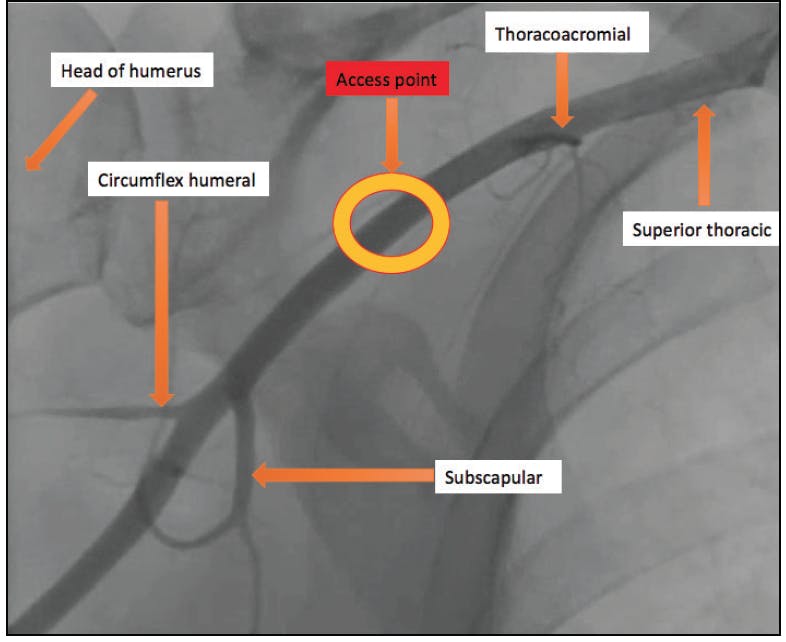

The axillary artery is a continuum of the subclavian artery, is extrathoracic lateral to the lateral margin of the first rib, and is easily accessible percutaneously. The artery can be divided into three parts. The artery supplies branches to the chest wall, its muscles, and then distally provides collaterals to the branchial artery in the event of occlusion of the axillary artery (Figure 1). Knowledge of the branches and the relationship of the brachial plexus in relationship to the axillary artery is essential in preventing neurovascular complications. The first part is lateral to the first rib, between the superior thoracic artery and the thoracoacromial artery, the second part is between the thoracoacromial artery and the lateral thoracic artery, and the third part is lateral to the lateral thoracic artery that supplies the subscapular artery. It is preferred to perform arteriotomy in the second part of the axillary artery and avoid the third part of the vessel. Arteriotomy in the first segment may also be performed without significant risk of brachial plexus injury; however, it may increase the risk of pneumothorax or intrathoracic access. In the second part of the vessel, the brachial plexus lies laterally and can be appreciated on ultrasound, which omits the risk of inadvertent injury during access. The second part and prior to the origin of the subscapular branch is considered the sweet spot; the subscapular artery provides collaterals to the brachial artery and prevents ischemia of the upper extremity in the event of stenosis or occlusion of the axillary artery proximal to this branch.

Figure 1. Anatomy of axillary artery and safe access point.8

Step 2. A 5- or 6-F sheath is placed in the ipsilateral radial or femoral artery in the standard fashion. The left subclavian artery or innominate artery is selectively engaged with a Judkins right (JR4) catheter. Regular angiography or digital subtraction imaging is performed to assess the axillary artery and its branches and the suitability for large-bore sheath insertion. This step is crucial to determine the zone of safe access, medial to the subscapular artery and lateral to thoracoacromial artery (Figure 1). An arterial roadmap could be utilized for safe access and to minimize contrast administration.